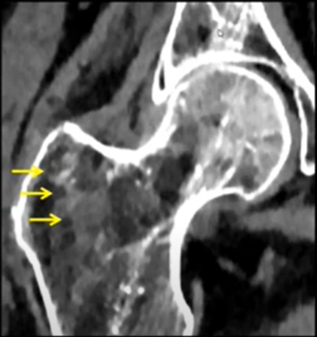

Hanche - anatomie, variante, coxarthrose, prothèse

VANDE BERG B. - UCL

Année académique 2021-2022

Musculo-squelettique Hanche DES SPECIALITE

Hanche et autour  ONTF, conflit, pathologie du sportif

MADANI A. – ULB